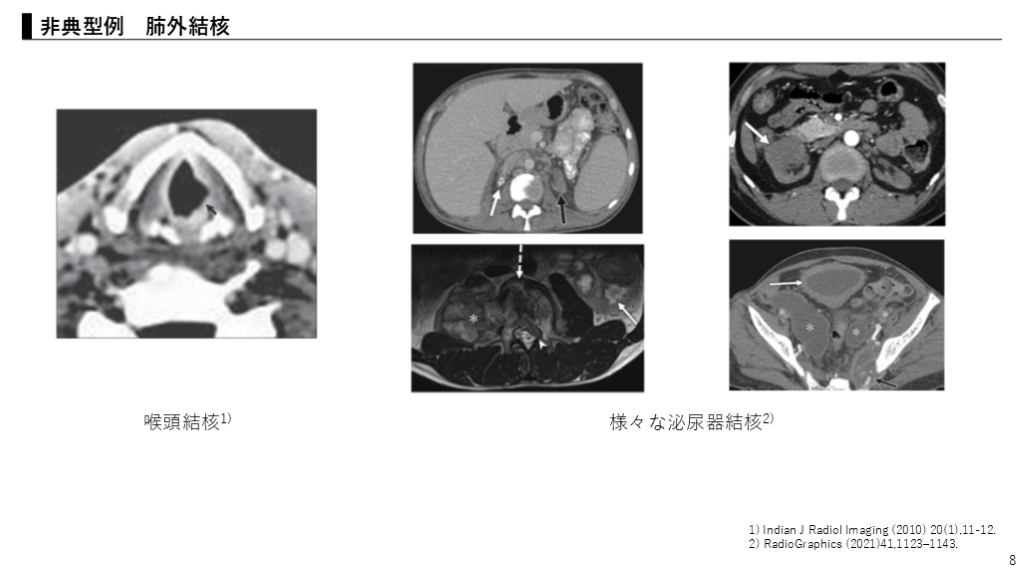

#8.

8 非典型例 肺外結核 喉頭結核1) 様々な泌尿器結核2) 1) Indian J Radiol Imaging (2010) 20(1),11-12. 2) RadioGraphics (2021)41,1123–1143.